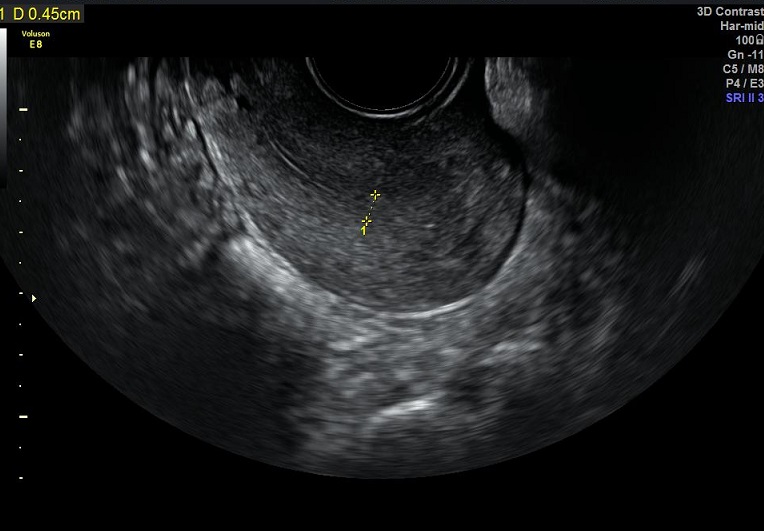

女性,30岁,继发性不孕2年,左侧输卵管宫外孕术后。常规二维超声子宫、卵巢及宫腔三维均未发现明显异常。宫腔置管后,宫腔水造影显示:宫腔稍见膨隆,内膜面光整,推注时有阻力。子宫输卵管实时三维超声造影显示:左侧输卵管未显示,右侧输卵管近端纤细,远端稍膨大,走行呈“S”行弯曲。诊断:左侧输卵管不通,右侧输卵管通而不畅。